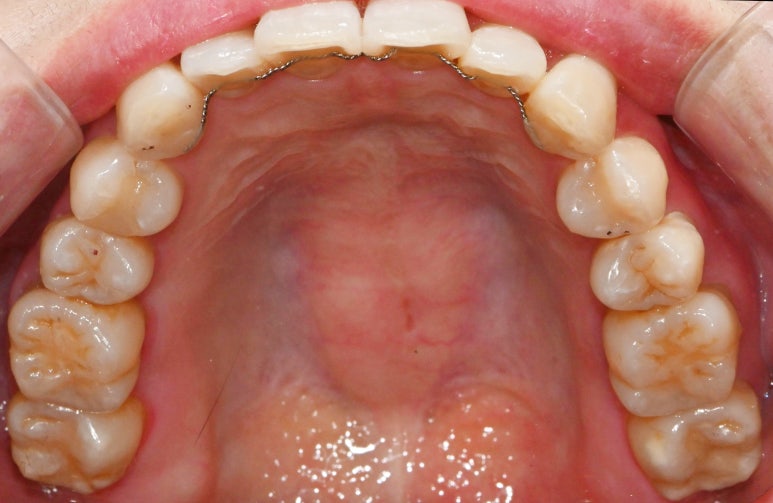

서울대입구역 교정 치과 에서

모든 진료가 끝나고 난 뒤

구내 모습을 보면

본래의 색과 비슷한 크라운을 올려드렸으며

저작 기능을 잘 수행할 수 있도록

적절한 사이즈의 보철을 제작하여

수복해 드렸습니다.

윗니도 마찬가지로

총생을 개선함과 동시에

본래의 자리로 돌아가지 않도록

안쪽에 유지 장치를 부착해두었습니다.

안쪽 면에 단단히 붙어있어

양치 관리를 잘 해주시면 되고,

정기검진을 통해

장치가 떨어지지 않았는지

확인해 주시면 된답니다.^^